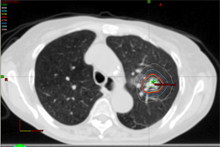

Plan

Radiosurgery plan ablating (treating to extremely high focal radiation dose) lung tumor.

Mrs. King – Stereotactic Radiotherapy/Radiosurgery for lung tumor

A 71-year old otherwise healthy active swimmer recently began experiencing dry cough after swims. Scans and biopsy confirmed an isolated early stage lung cancer. Despite her good health, patient did not wish to consider chest surgery.

For patients with early stage lung cancer, advanced high dose and highly focused radiation therapy can achieving excellent cure rates comparable to surgery, representing a non-invasive therapy with minimal risks and side effects

An advanced radiation technique termed stereotactic radiotherapy/radiosurgery was customized for Mrs. King. This allowed the curative treatment of his tumor, while minimizing radiation dose and side effect risks to the heart, esophagus, and lungs.

She tolerated therapy well and continued swimming during and after therapy.